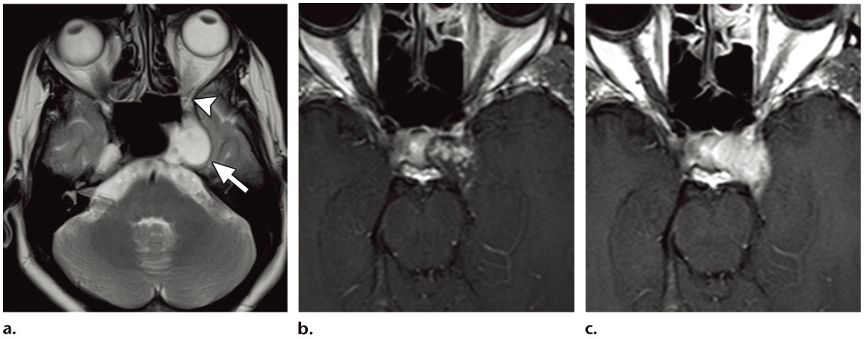

Figure: Cavernous hemangioma in a 40-year-old woman with decreased vision in the left eye that had been present for 6 months. No other clinically important cranial nerve deficits were seen. (a) Axial T2-weighted MR image shows a homogeneous hyperintense mass (arrow) in the left cavernous sinus and the left trigeminal cave (Meckel cave). The superior orbital fissure (arrowhead) is not involved. (b) Axial T1-weighted MR image obtained 2 minutes after contrast agent injection shows central enhancement within the lesion. (c) Axial T1-weighted MR image obtained 9 minutes after contrast agent injection shows complete fill-in of contrast agent, with homogeneous enhancement. (Note that the gadolinium-enhanced images in b and c have a different axial orientation, compared with the axial T2-weighted image in a.)

At MRI, cavernous hemangiomas are characterized by high signal intensity on T2-weighted and FLAIR MR images. Dynamic contrast enhanced T1-weighted MR images show characteristic progressive “fill-in” of contrast agent, with intense homogeneous enhancement on late gadolinium-enhanced MR images. Hemangiomas encasing the cavernous segment of the ICA usually do not cause luminal narrowing of the ICA, in contrast to meningiomas, which tend to cause luminal narrowing of the ICA. Scintigraphic imaging after administration of 99mTc pertechnetate–labeled red blood cells demonstrates accumulation of tracer within the lesion, a finding that is said to be specific for making the diagnosis of cavernous hemangioma. Digital subtraction angiography may show hypertrophic branches from the ICA and the external carotid artery, as well as variable vascular blush. Establishing the diagnosis of cavernous hemangioma before surgery is of paramount importance, because these tumors are notorious for causing profuse and often uncontrollable intraoperative hemorrhage.